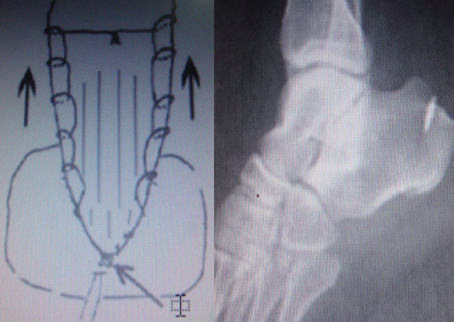

带线锚钉在中踝外科的应用

应用范围:

• 单纯下胫腓联合分离

• 跟腱止点撕脱

• 第五跖骨基底部撕脱性骨折等

1.带线锚钉单纯下胫腓联合分离

下胫腓联合由下胫腓前韧带、后韧带、下横韧带及最坚固的骨间韧带紧密连结构成。下胫腓联合分离是由于踝关节受强力外翻外旋暴力所致,可单独发生,但多合并踝关节其他韧带损伤或骨折、脱位。如治疗不及时或处理不恰当,常遗留慢性疼痛、关节不稳及创伤性关节炎,严重影响踝关节功能。

传统法:下胫腓联合分离手术固定方法很多,有螺钉、生物可吸收植入物、腓骨钩、线扣固定等。

带线锚钉法:

①创伤小,在外踝上方作2 cm小切口,不用二次取出。早期负重,出现断钉情况很少;

②编织线的弹性模量与螺钉、可吸收螺钉相比更接近韧带;

③编织线与骨间韧带方向相一致,类似于韧带的力学重建。同时在腓骨上编织线的走行与腓骨纵轴一致,这样即使编织线对腓骨有切割也不容易引起腓骨的骨折。